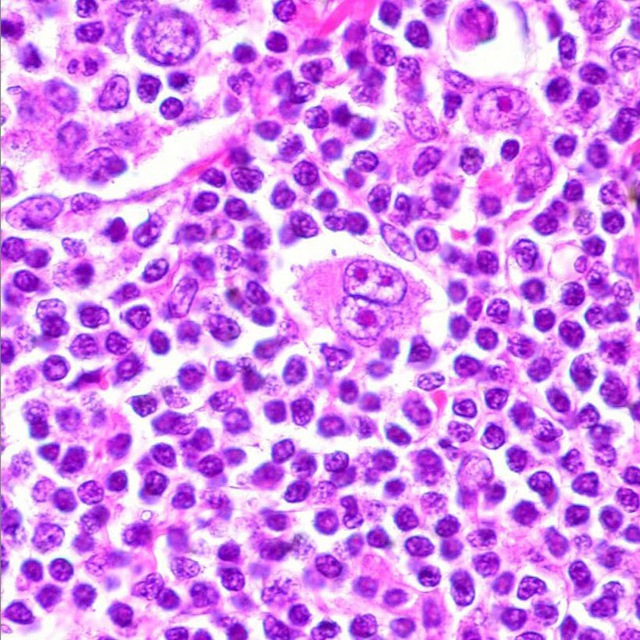

Микропрепараты: Лимфогранулематоз и Нодулярный Склероз

Раздел: Секреты мастерства